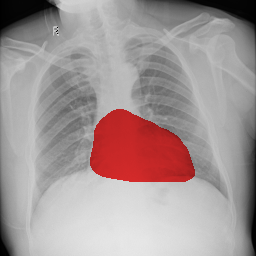

The task of chest organ segmentation is a simple benchmark task in medical image segmentation. In this task, we consider three semantic classes, namely left lung, right lung, and heart. We can easily control the environment to get an insight into the impact of the limited partial labels on various representative partially supervised methods and the efficiency of VLUU. Without specification, the experimental comparison is conducted in such a way that different models use the same network backbone, loss function, training strategy, and the set of hyperparameters.

We use three partially labeled datasets as the training set and one fully labeled as the test set, where the four datasets are collected from four different sources. We choose this setup to simulate the practical scenarios where dataset shift exists, which is a challenging situation for DL models. We use the JSRT dataset as the left lung dataset, denoted as L. We use a subset of the Wingspan dataset containing 18 CXRs as the right lung dataset, denoted as R. We use another subset of the Wingspan dataset containing 18 CXRs as the right lung dataset, denoted as H. We use the rest of the Wingspan dataset as the fully labeled test set, which contains 185 CXRs, and denote it as T. The visual comparison of the data modalities of the four sets can be viewed in Fig. 5. Note, all four sets are collected from 4 different sources (hospitals with different imaging protocols).

5.1.4 Comparison Under Small-Scale Data

It is worth mentioning that, MBG, IMBP, EL, and VLUU are end-to-end methods, i.e. they do not require any auxiliary NNs or multi-stage training procedures. We provide the qualitative comparison of end-to-end methods in Fig. 6(a). VLUU tends to output more realistic masks than the STOA method EL in terms of the location and shape.